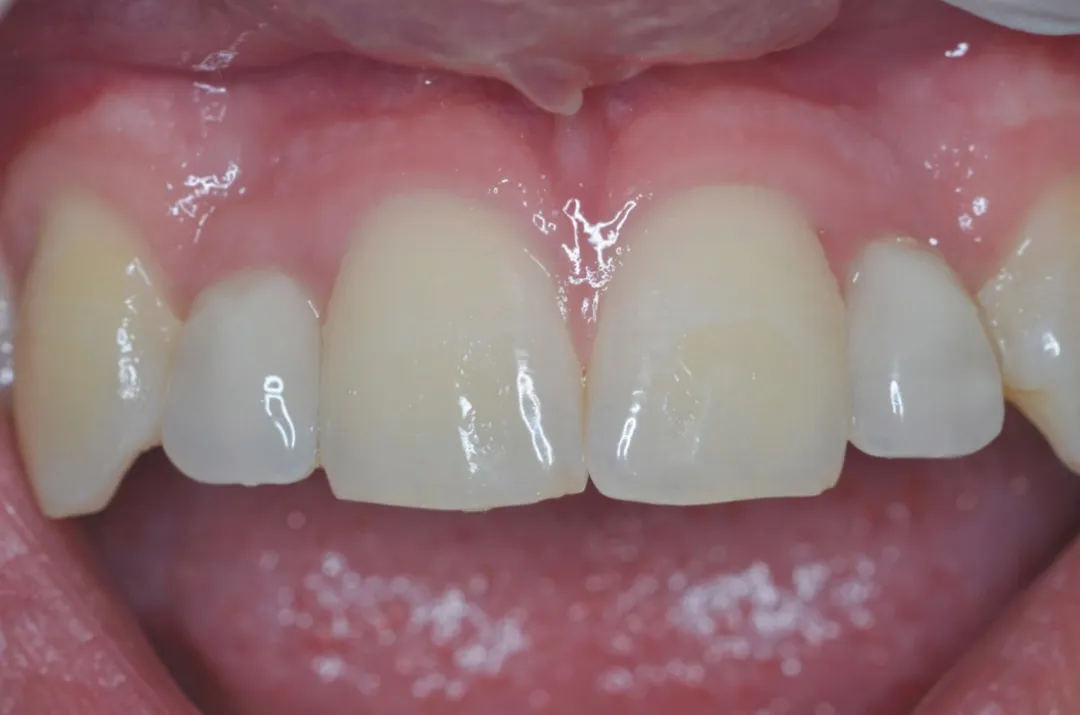

3 号病例 - Patrick EXBRAYAT 医生(图 36 至 49)

女性患者,侧切牙 12 发育不全,长期使用临时修复手段。

图 48 :术后 1 年口内情况。